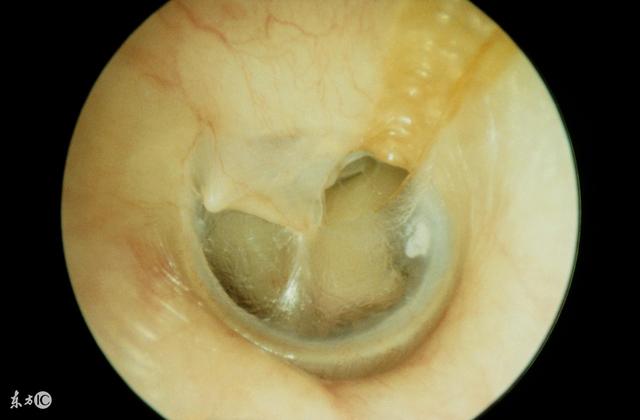

鼓膜穿孔图片

鼓膜置管后常出现的并发症有耳漏,鼓膜穿孔,鼓室硬化,鼓膜内陷和

鼓膜内陷